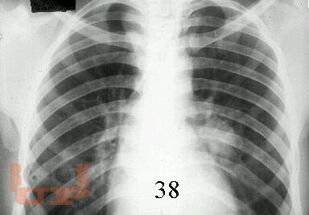

Первичный туберкулез

В предлагаемом учебно-методическом пособии рассматриваются вопросы клиники, диагностики, дифференциальной диагностики первичных форм туберкулеза.